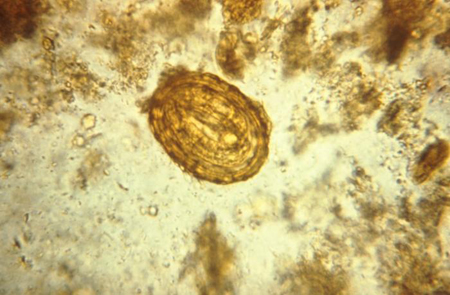

Quando presentes no exame direto ou em uma amostra concentrada, os ovos geralmente são esféricos ou ovais, de superfície irregular, de coloração amarelo-amarronzada e medem de 60 a 70 micrômetros.[1] Pode ser mais difícil identificar ovos não fertilizados em razão de seu tamanho e aparência atípicos.[Figure caption and citation for the preceding image starts]: Fotomicrografia revelando ovo fertilizado do parasita Ascaris lumbricoidesPublic Health Image Library, CDC [Citation ends].

O exame negativo não exclui ascaríase, principalmente quando a infecção é causada apenas por vermes machos, durante as fases migratórias, e se realizado antes da maturação completa dos vermes adultos (8 semanas após a exposição).

Pelo grande número de ovos produzidos por cada verme adulto fêmea, o exame de uma única amostra fecal geralmente é diagnóstico. Entretanto, a microscopia das fezes produz resultados falso-negativos em infecções por vermes adultos do mesmo sexo ou infecções por vermes jovens.[24][25]